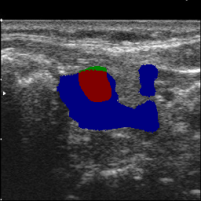

3.3 High-confidence Multi-level labels Generation

According to Reference 1 and Reference 2 discussed in Sec. 3.2, weakly supervised segmentation requires nodule location labels for location learning and region distribution labels for shape learning. In this section, we integrate geometric transformations of point annotations and segmentation from prompted MedSAM to generate high-confidence location labels for location learning in Eq. (1), as well as high-confidence foreground labels and background labels for shape learning in Eq. (2) and Eq. (3).

Specifically, as illustrated in Fig. 1, in the high-confidence labels generation phase, we derive three geometric transformations representing low-level topological information from clinical annotations:

The regions that contain high-level semantic information are generated by prompted MedSAM:

Finally, we fuse the initial topological shape ex-rectangle , in-quadrilateral , and out-rectangle and results from prompted MedSAM to generate high-confidence location , foreground , and background labels .

| (4) | ||||

where denotes the logical OR operation applied to the positions of two masks, while represents the logical AND operation.